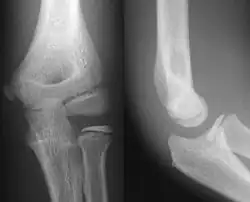

- Elbow - AP and Lateral. Radial head projections available on request

- Knee - AP and Lateral. Intra Condular projections on request

Right knee, anteroposterior -

Right knee, lateral -

Patella, (slightly skew) skyline